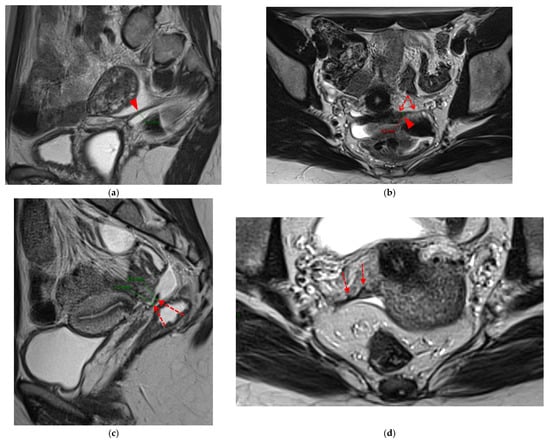

A type 5 USL appears nodular and can be classified either as type 5A or type 5B.

A type 5A USL (Figure 6) is nodular with a smooth contour.

HTD Type 5B USL

A type 5B USL (Figure 7) is nodular with spiculated margins. A type 5B USL may also display an isolated nodule with microcystic content.

Figure 6. Pelvic MRI scans of two patients with HTD type 5A USLs. (a,b) Sagittal T2WI: nodularity with regular margins (arrows) within the right USL (arrowheads).

Figure 7. Pelvic MRI scans of two patients with HTD type 5B USLs. (a) Patient 1: sagittal T2WI shows a microcystic nodule (arrow) within the origin of the right USL (arrowhead). (b,c) Patient 2: axial (b) and sagittal (c) T2WI show a nodular left USL with spiculated margins (arrow) and a right ovarian endometrioma (arrowhead).